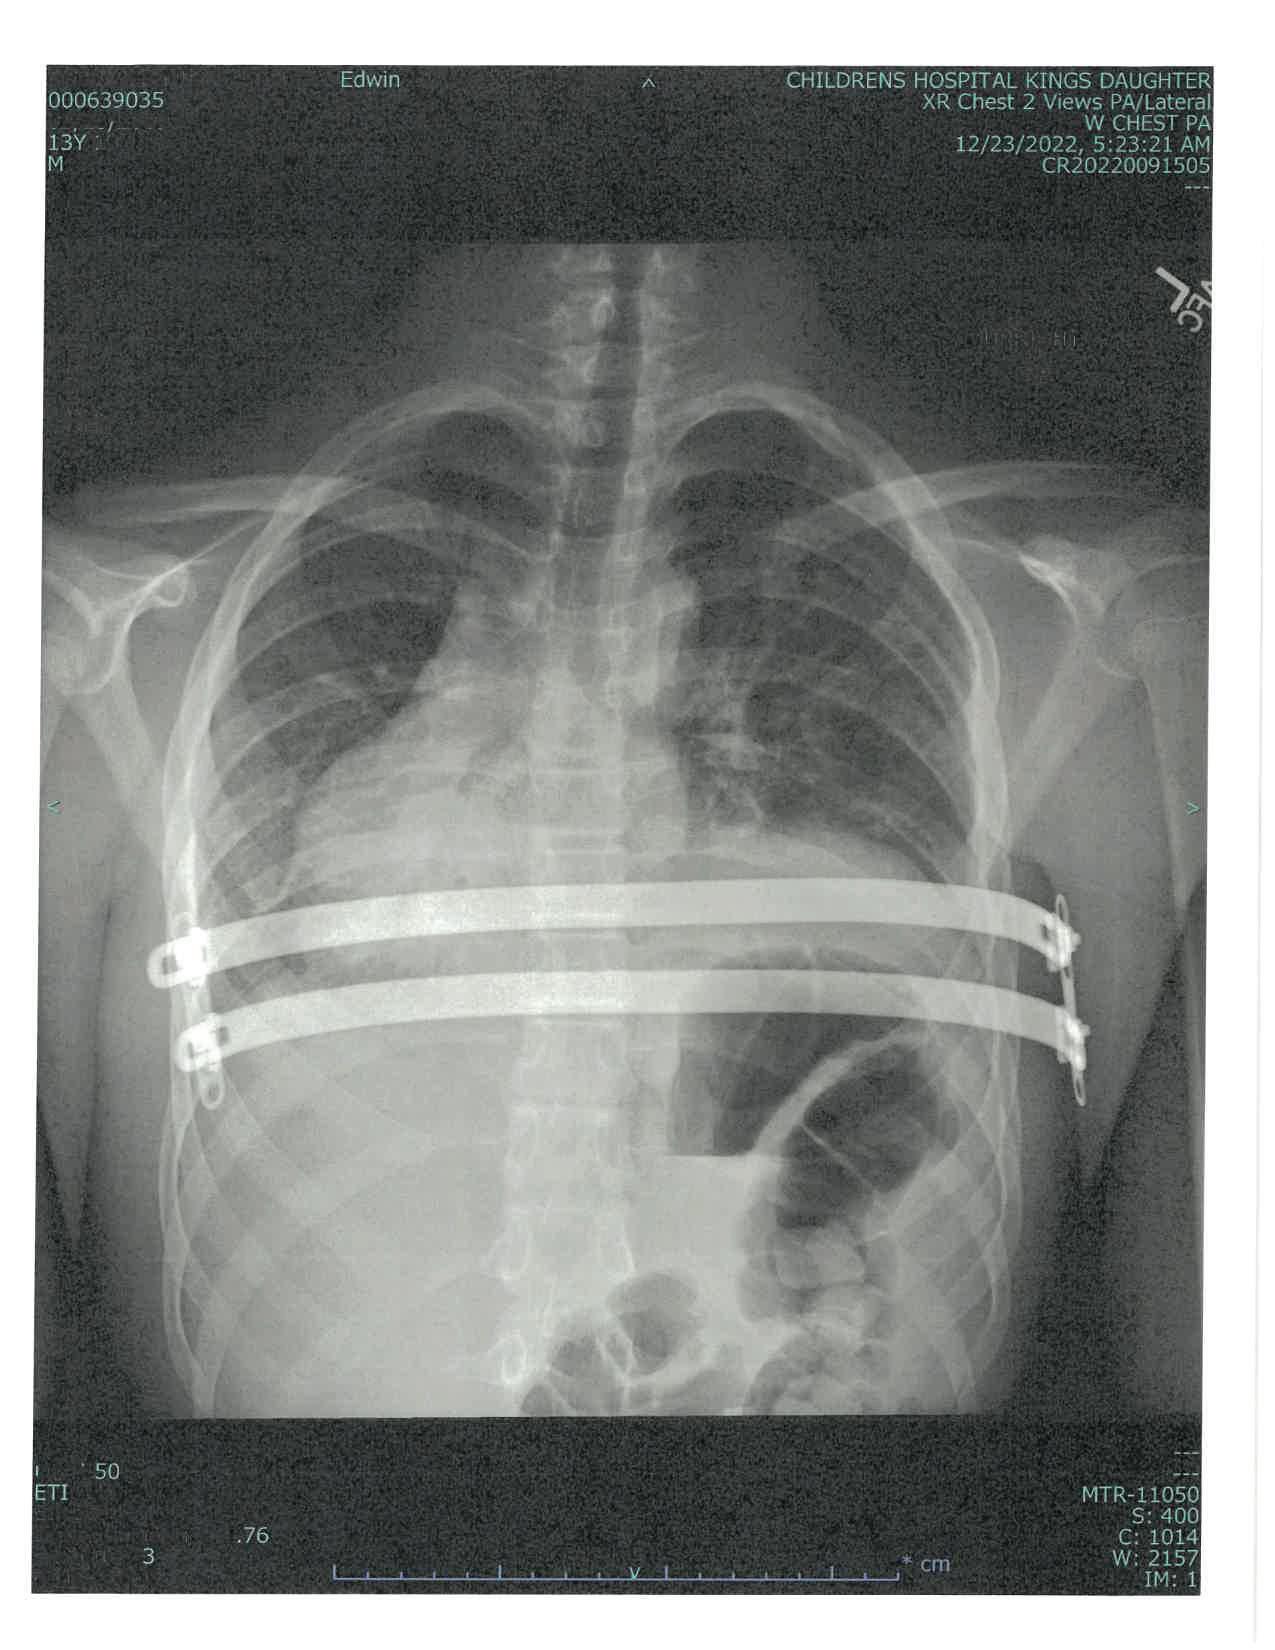

Thomas Marlowe-Santiago finds new confidence after chest wall reconstruction and years of specialty treatment at CHKD

Thomas Marlowe-Santiago has been coming to CHKD since the day he was born, when doctors in the delivery room noticed something odd about his heartbeat: it was loudest on the right (or in this case, wrong) side of his chest.

Thomas has a condition called situs inversus, which means his internal organs are on the opposite side of the body from those with normal anatomy. This mirror-image flip is one aspect of a genetic condition that Thomas has called Kartagener syndrome, which also involves dysfunction of cilia, tiny hair-like structures that are essential for a wide range of functions in the body. In Thomas’ case, this dysfunction causes him to experience frequent respiratory and sinus infections.

Since his first transfer to CHKD’s Neonatal Intensive Care Unit, Thomas has been hospitalized at CHKD several additional times for pneumonia and bronchitis. Over his 16 years, the Virginia Beach teen has been treated by a host of specialists at CHKD, including pulmonologists; cardiologists; ear, nose, and throat surgeons; and allergy, asthma, and immunology specialists. He does physical therapy every day, wearing a special vest that vibrates to help dislodge mucus and keep his lungs clear. He also takes medications for asthma and allergies.

But that’s not all this brave young man has had to deal with. He also has Poland syndrome, which is characterized by a missing pectoralis muscle, in his case on his left side. And, as a teen, Thomas developed pectus excavatum, a condition in which the chest wall sinks in toward the spine.

Fortune was on Thomas’ side in another respect, however. His hometown, go-to hospital that has treated him since birth just happens to be the top international center for the treatment of pectus excavatum.

Thomas’ case definitely fell into the “most complex” category, says CHKD surgeon Dr. Franklin Margaron, who treated Thomas. “Thomas’ muscular asymmetry and underlying respiratory issues presented challenges,” says Dr. Margaron. “When you and I inhale, our sternum expands outward,” he explains. “Thomas’ sternum rotated inwards toward his heart and lungs when he inhaled.

“Severe pectus excavatum like Thomas’ can cause direct cardiac compression, which can lead to valvular dysfunction, arrhythmias, and a number of different problems,” says Dr. Margaron. “For Thomas, that would have potentially led to shortness of breath and

inability to engage in activities he would otherwise be able to do.”

In addition, the chest can be very sensitive for weeks after the Nuss procedure. Surgeons use curved metal bars that go under the sternum and are affixed to ribs to press the sternum and ribs out into a normal shape. The bars remain in place for several years while the chest wall matures and hardens.

Dr. Margaron was concerned that the agitation from Thomas’ compression vest might be very painful, or even dislodge the Nuss bars from their proper position. But if Thomas doesn’t use his vest every day, he risks developing lung infections, including pneumonia.

“Thomas’ unique physiology called for a dramatic degree of correction combined with the most stability we could offer,” says Dr. Margaron.

For Thomas, Dr. Margaron opted to use a system of surgical instruments and implants developed in Korea by Dr. Hyung Joo Park. The Park system is a variation of the Nuss procedure that uses additional bars and a different system of anchoring them to offer additional stability.

Thomas went into surgery on December 20, 2022. “This was the first major surgery that my son ever had. I was petrified that something would go wrong,” says Lisa

Since having metal bars placed into his chest to reshape his sternum, Thomas says he can finally take a deep breath. After three years of follow-up checkups and imaging, he expects to have the bars removed in early 2026.